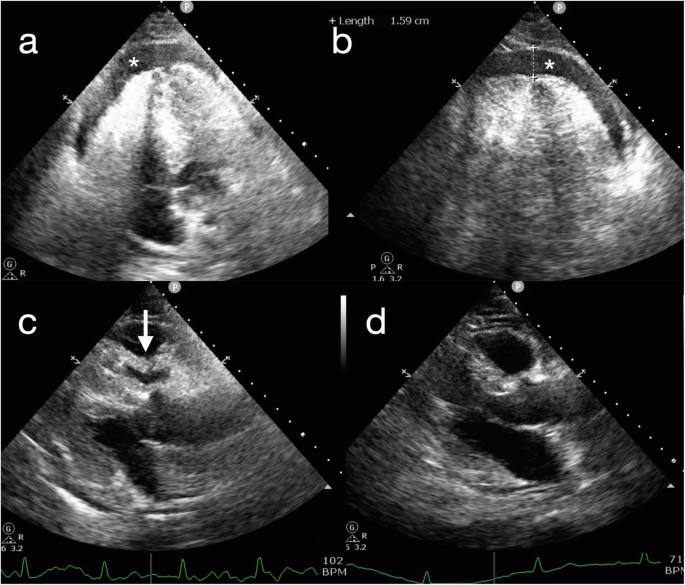

A 47-year-old man presented for inferior vena cava (IVC) filter removal, which was initially placed roughly one month prior to this hospitalization. He had a 10 pack-year history of smoking and was diagnosed with thromboangiitis obliterans for more than six months. At that time, the patient had right leg deep vein thrombosis (DVT) and bilateral segmental pulmonary embolism (PE). A nonpermanent IVC filter was placed to prevent recurrence of PE from DVT, and the DVT was treated with mechanical thrombectomy. Subsequently, the patient received long-term anticoagulation with rivaroxaban. In the present hospitalization, computed tomography pulmonary angiography (CTPA) showed that the bilateral segmental pulmonary thrombus had almost disappeared, and ultrasonography showed partial thrombus dissolution and patency of blood flow in the vein of the right lower limb. Based on the above results, it was not necessary to retain the filter. Then, interventional radiology-guided IVC filter removal was performed in the operating room. Under X-ray fluoroscopy, a snare was inserted into the right internal jugular vein, and the IVC filter was withdrawn from its hook. The procedure was uneventful. Within 30 min after the procedure, the patient developed chest pain, nausea, vomiting and presyncope. Physical examination showed a blood pressure of 70/34 mmHg, a pulse of 108 beats per minute, and a respiratory rate of 23 breaths per minute. Arterial blood gas showed a pH of 7.31, PaCO2 of 36 mmHg, PaO2 of 68 mmHg, HCO3 of 18.1 mmol/L, lactate 5.8 mmol/L and oxygen saturation of 95 %. Bedside echocardiography confirmed circumferential pericardial effusion, 1.59 cm in the largest dimension, with evidence of cardiac tamponade (Fig. 1, videos in supplementary files 1 and 2). The ideal puncture site, as defined by echocardiography, was para-apical. Pericardiocentesis was immediately performed with an 18G (1.3 × 1.06 × 65) mm needle after echocardiography localization. Confusingly, only 3 mL of bloody pericardial effusion was removed in total, and subsequently, the patient’s symptoms significantly improved except for mild subxiphoid pain. His vital signs improved approximately 3 min later, with a blood pressure of 125/95 mmHg, a pulse of 70 beats per minute, a respiratory rate of 20 breaths per minute, and an oxygen saturation of 99 %. Clotting tests indicated an INR of 1.15, an activated partial thromboplastin time of 34.7 s, and a prothrombin time of 14.5 s. Repeat echocardiography revealed that the pericardial effusion had disappeared (Fig. 1d, video in supplementary file 3). To clear up the confusion, an urgent CTPA was performed approximately 3 h after the procedure. The images showed mediastinal effusion, which had not been seen on the previous CTPA (Fig. 2a), around the left ventricle in the anterior mediastinum (Fig. 2b). Considering that the patient was asymptomatic and organ failure secondary to mediastinal effusion were not present, no intervention was suggested. He remained in the hospital for three days after the procedure. He was subsequently discharged in a stable condition, and outpatient follow-up was advised.

Echocardiography with a four-chamber view and a parasternal long axis. Circumferential pericardial effusion (*) (Panel a) was 1.59 cm in the largest dimension (Panel b). Sign of cardiac tamponade (Panel c): diastolic collapse of the right ventricle with pericardial effusion (white arrow). The pericardial effusion disappeared after the pericardiocentesis (Panel d)